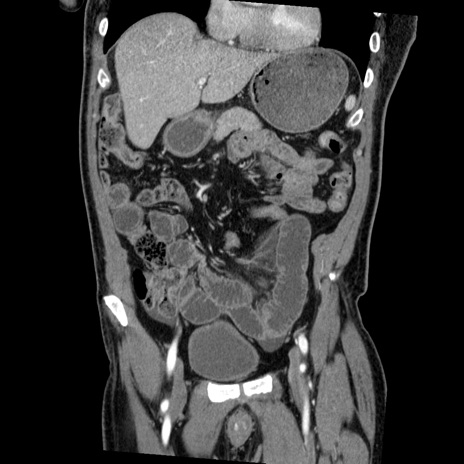

症例22(冠状断像)

【症例】50歳代男性

【主訴】腹痛

【現病歴】AVMからの被殻出血のため回復期リハ病棟入院中。 本日午後3時頃急に下腹部痛が出現した。

【既往歴】AVM、被殻出血、虫垂炎、高血圧

【身体所見】意識晴明、左半身不全麻痺、会話の理解は良好、36.5°C、腹部:膨隆、全体に板状硬、下腹部正中に圧痛点あり、反跳痛-、筋性防御不明、右下腹部にope scar

【データ】WBC 9400、CRP 0.06